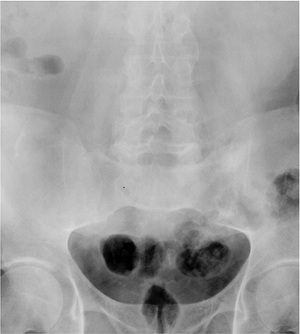

![]() |

FIGURE 13-14

Enteric arthropathy. AP radiograph of the spine and sacroiliac joints showing inflammatory arthropathy symmetrically involving the sacroiliac joints. |